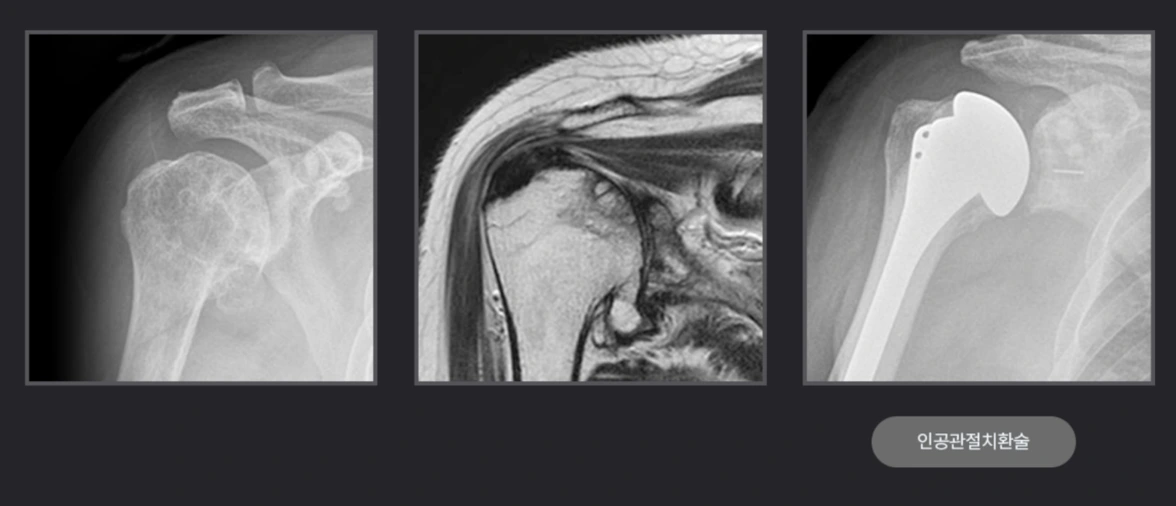

“어깨관절염 치료로는 초기에는 비수술적치료를 우선 적용하지만 증상이 심해지면 관절내시경으로 파열된 힘줄을 봉합해 염증을 없애는 수술이나 심한 관절염이 발생한 어깨관절을 인공관절로 교체하는 인공관절 치환술을 고려해야 합니다”라고 김학수 원장님이 알려주시네요.

캡처.PNG